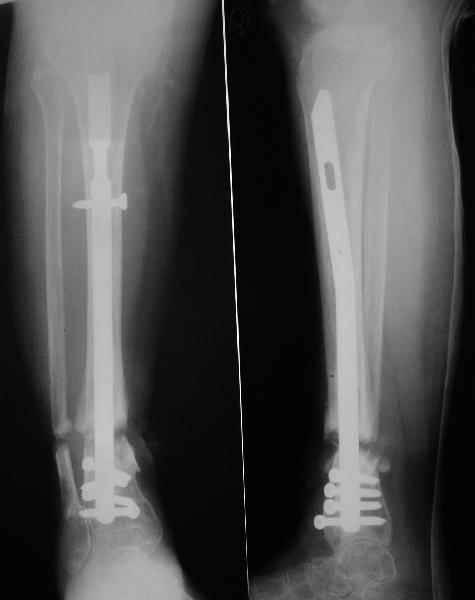

Аппарат - чтобы плавно исправить ось. В приложении - снимки на момент окончания коррекции в аппарате, фото с операции, и послеоперационная рентгенограмма.

Диаметр гвоздика 10,5 мм. Пришлось укорачивать до 23 см - уж очень миниатюрная дама, отверстия насверлил под 45 градусов, под 5 мм винты. По оси удалось сблизить до этого положения. Заперли гвоздь пока статически с планом через 2 месяца верхний винт убрать. Но это ей придется уже в Ташкенте сделать. Что скажете? Спасибо.

In attachment - x-rays at the end of alignment, the surgery, and result. The nail was cut to 23 cm. Four 45 degree holes were pre-drilled at the distal nail tip. The nail was locked statically

after some impaction. Dynamization is considered in 8 weeks. Any comments/critics?

Отправитель: Alexander Chelnokov 27 Апрель 2005, 02:09

А вдруг там все-таки от дистракции образуется регенерат, хоть дохленький? На созревание и зарезервировали 2 месяца стабилизации.

Если регенерата совсем не будет - после отпирания гвоздя отломки начнут сближаться до полного контакта. А если все-таки будет - еще и ~1 см выиграем.

Отправитель: Nuno Craveiro Lopes 27 Апрель 2005, 02:10

Alex,

> In attachment - x-rays at the end of alignment, the surgery, and

> result. The nail was cut to 23 cm. Four 45 degree holes were

> pre-drilled at the distal nail tip. The nail was locked statically

> after some impaction.

Amazing! How can you find the pathway of the nail through all those wires and the distal screws through so much hardware?

Отправитель: Alexander Chelnokov 27 Апрель 2005, 02:57

NL> Amazing! How can you find the pathway of the nail through all those wires

NL> and the distal screws through so much hardware?

Some wires were intentionally inserted to leave needed space for the nail, some were removed at the moment of nail insertion. I inserted one distal screw and then removed the frame, then inserted rest ones.

NL> Deep infection rate must be high...

Why? There were no signs of infection and ex-fix has been in place for only 2 weeks.

NL> If you dynamise before regenerate maturation, d'ont you loose lenght?

Sure. Frankly speaking the target was just functional stable aligned limb regardless of shortening. I don't expect regenerate appearance, but what if i am wrong? If the bonus appears in the gap, we'll give it 2 month to mature. Anyway x-rays will be taken prior screw removal so dynamization can be postponed if necessary.